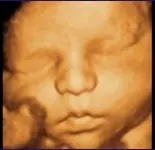

Ecografia 4D

La ecografía 4D es el más reciente desarrollo tecnológico que suma a las posibilidades diagnósticas de la ecografía tradicional 2D y la ecografía tridimensional 3D. Su nombre de 4D no implica una nueva dimensión, sino que ha sido escogido para diferenciarla de la 3D anterior que reconstruye una imagen estática. El cuarto componente alude al tiempo ya que se obtiene una secuencia de imágenes tridimensionales en movimiento, permitiendo de esta manera un mejor seguimiento y representación de la actividad fetal. Diagnus, ha tenido el privilegio de ser pionero en la introducción de este método en Argentina estando no solo en la vanguardia de lo científico sino también en lo tecnológico.

Esta nueva función de los ecógrafos se realiza con igual principio físico que la ecografía tradicional y por lo tanto continúa siendo un método inocuo para la madre y el niño.

Es la posibilidad de obtener un estudio de alta calidad en un ámbito distendido, compartiendo una experiencia única. Es posible espiar el comportamiento del feto dentro del útero, como por ejemplo su sonrisa o sus muecas con mayor precisión y definición que una ecografía tradicional constituyendo un momento de encuentro familiar. (Es factible también grabar un recuerdo en video o almacenar imágenes seleccionadas en formato JPEG).

A principios del segundo trimestre se obtiene una visión más integral del feto en su medio ambiente, y a medida que avanza la gestación el campo de visión se va reduciendo pero con mayor definición y madurez de los rasgos faciales. Hacia el final de la gestación el tamaño fetal, la disminución proporcional del líquido amniótico, la posición fetal y la compacta mineralización ósea, disminuyen las condiciones de visualización.

La edad ideal para la visualización podemos decir que está alrededor de las semanas 23 a 27 de gestación donde la proporción de líquido amniótico es adecuada y el tamaño fetal intermedio.